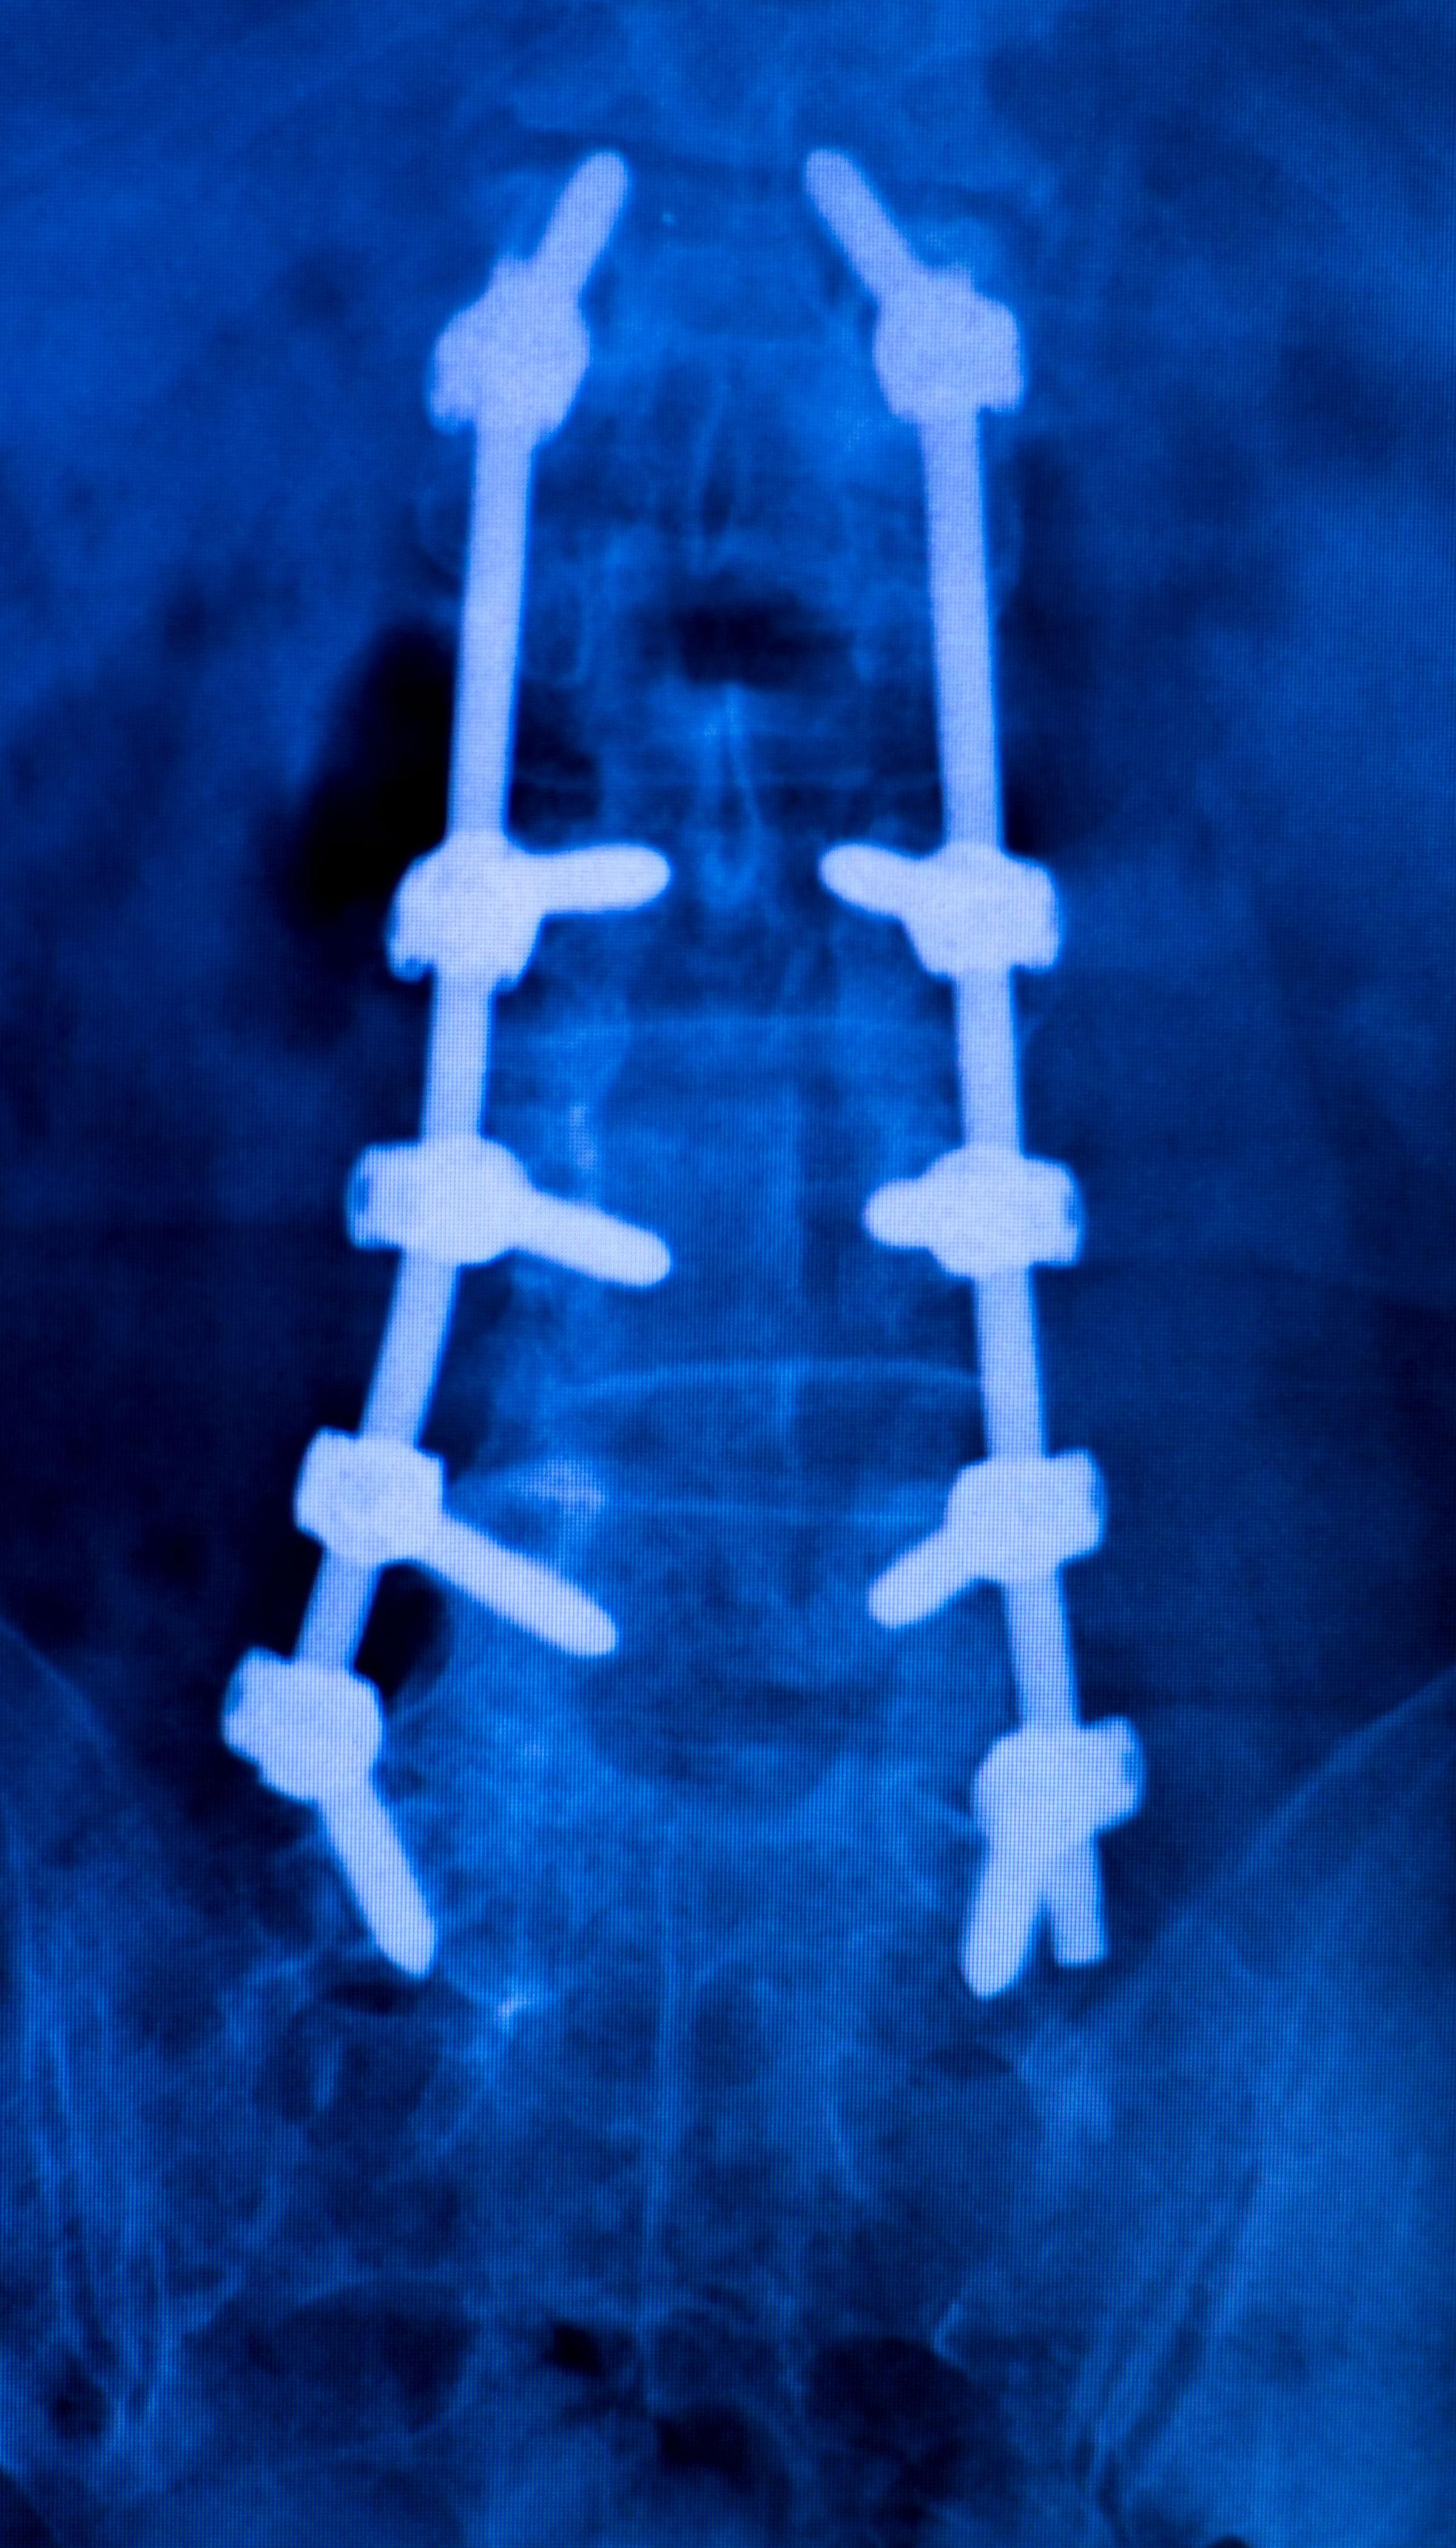

Спондилодезные имплантаты соединяют два или более позвонков вместе. Эти устройства сохраняют устойчивость позвоночника и помогают при боли. Вам может понадобиться спондилодез, если у вас дегенеративное заболевание дисков, травма или спондилолистез. Некоторыми распространенными имплантатами позвоночника являются транспедикулярные винты, стержни, пластины и межтеловые клетки. Эти устройства удерживают кости на месте, пока они заживают и срастаются.

Пластины: Пластины соединяют кости и удерживают их в устойчивом состоянии во время сращения.

Стержни: Стержни скрепляют позвонки и помогают исправить форму позвоночника.

Винты: Винты прикрепляют пластины и стержни к костям.

Если вам предстоит операция по спондилодезу, ваш врач может использовать стержни, винты или клетки. Эти устройства удерживают ваши кости на месте. Они помогают вашему позвоночнику правильно восстановиться и восстановиться.

Спинные имплантаты помогают решить такие проблемы, как сколиоз или кифоз. Эти устройства сохраняют прямой позвоночник во время выздоровления. Врачи используют стержни, винты и крючки, чтобы выпрямить позвоночник и удерживать его на месте.

Имплантаты удерживают позвоночник в правильном положении во время выздоровления.

Они работают со спондилодезом, чтобы держать позвоночник прямым в течение длительного времени.

При сколиозе хирургическое вмешательство выпрямляет позвоночник и использует имплантаты, чтобы сохранить его устойчивость.

При кифозе имплантаты помогают вернуть естественный изгиб и сделать позвоночник стабильным.